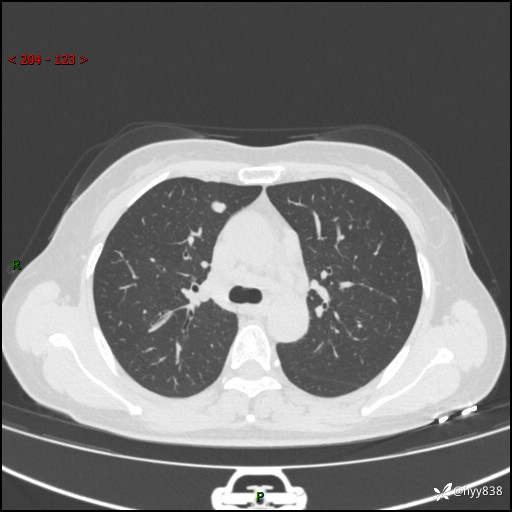

【患者信息】:58岁/女

【主诉】:体检发现肺结节

【检查】:胸部CT平扫+增强

结节病 (44)

小细胞癌 (19)